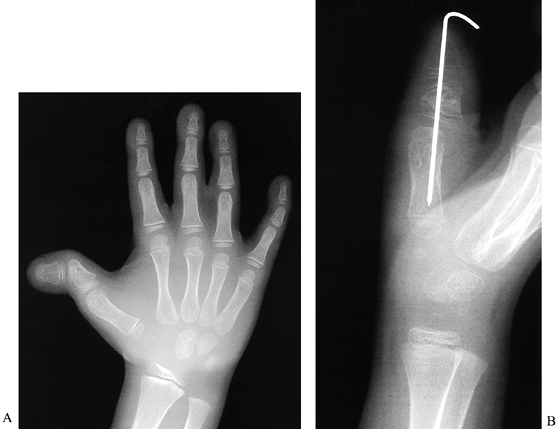

![]() |

Figure 69.3. Thumb polydactyly. A: Type I. B: Type II (although the two distal phalanges are joined by cartilage at the base). C: Type IV, preoperative. D: Type IV. E: Type IV, postoperative. F: Type VI. G: Type VI. H: Type VII.

single epiphysis (Fig. 69.2) (110).

Figure 69.4. Horii et al.’s subdivisions of Wassel type IV thumb polydactyly into four types.